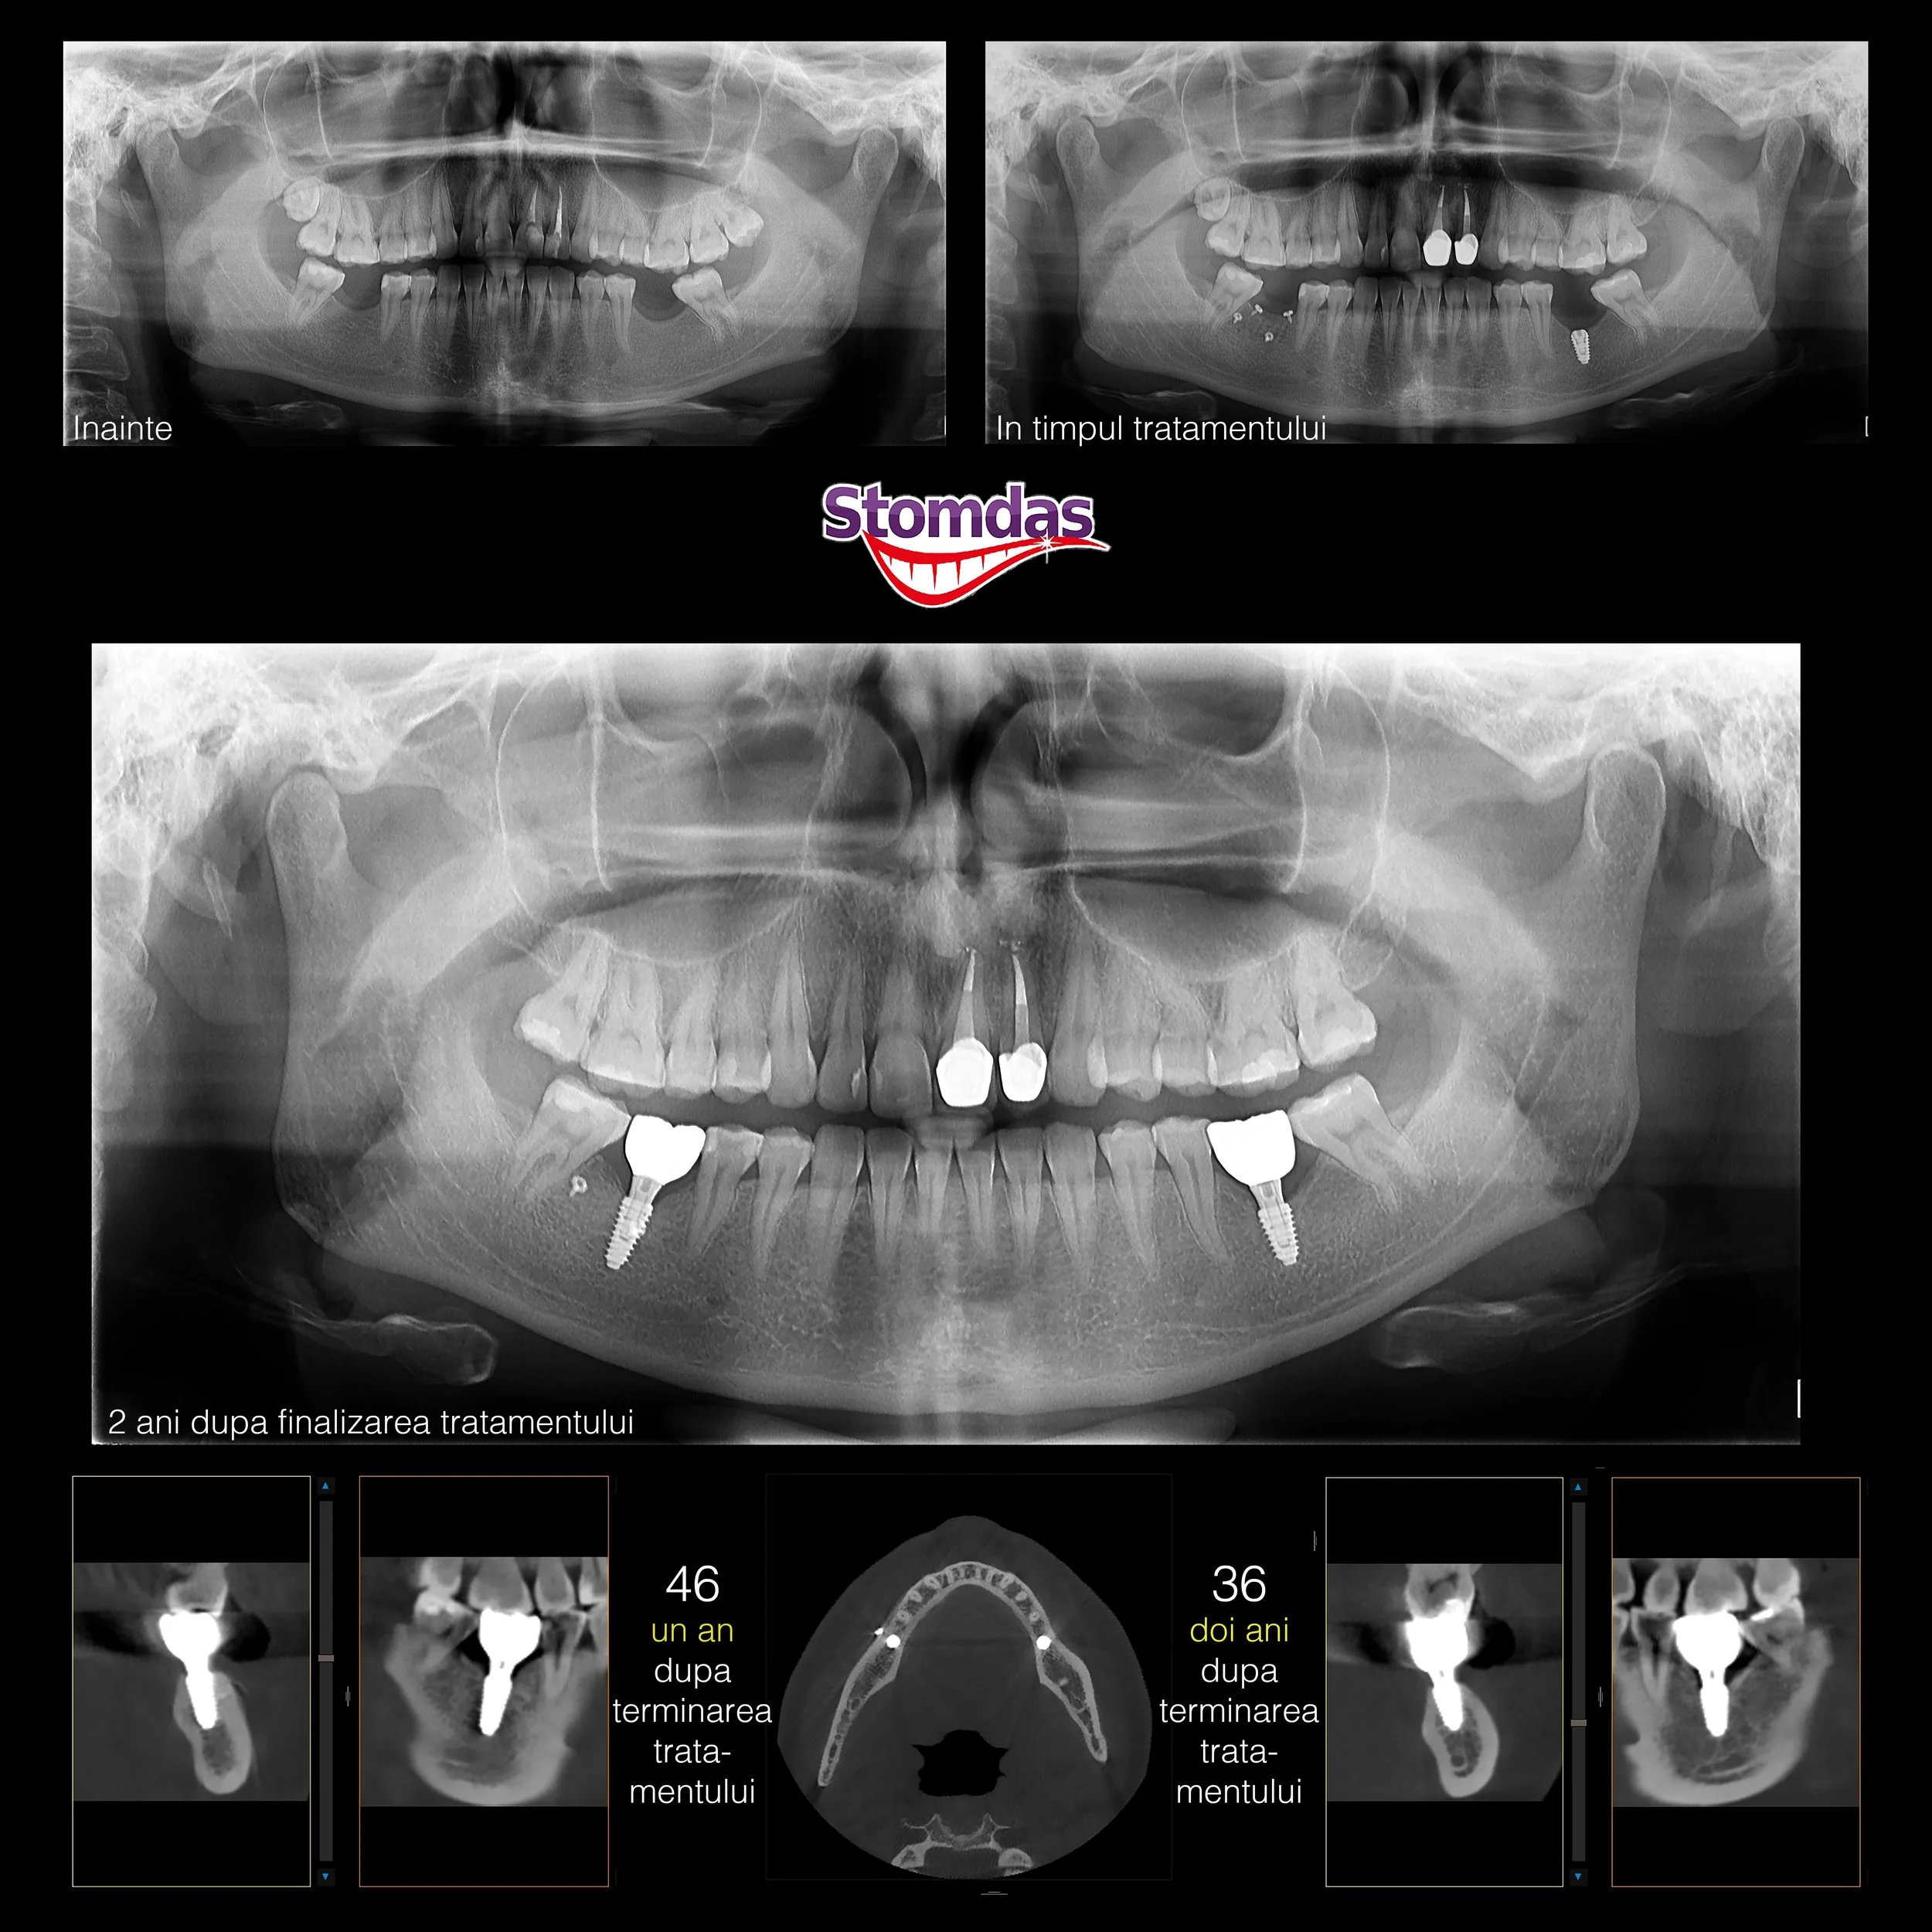

IMPLANTOLOGIE